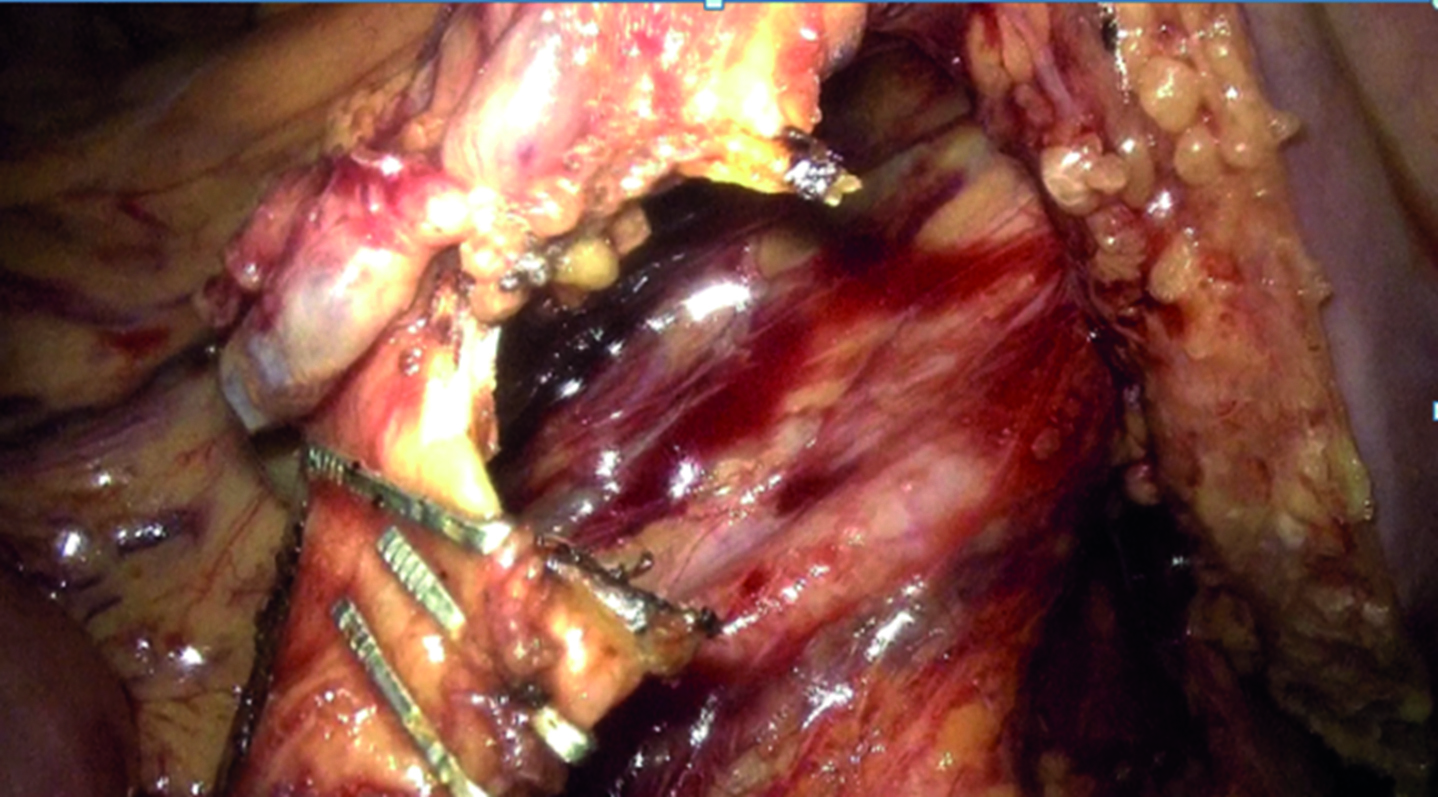

Findings of laboratory examinations: the level of carcinoembryonic antigen (CEA) was 26.07 ng/ml, and the level of cA 19-9 was 3.7 units/ml. Findings of magnetic resonance imaging (MRI) of the pelvic organs with contrasting (Fig. 1): in the rectum, at the height of 95 mm from the anus and higher, at a length of approx. 80 mm, there is a deformation and an uneven infiltrative thickening of the walls up to 20 mm that affected all layers, with a moderate obstruction of the bowel lumen; with intravenous contract administration, it accumulated the contrast in an unevenly intensive way. In the affected area, the outer contours of the bowel are uneven and indistinct, with signs of invasion to the mesorectal fascia. Pelvic vessels have no pathological changes. Enlarged mesorectal lymph nodes up to 11×7 mm are visualized. Conclusion: locally advanced rectum cancer, metastases to mesorectal lymph nodes; benign hyperplasia of the prostate.

Figure 1. MRI of the pelvis. Picture of locally advanced rectal cancer (indicated by arrows).

Рисунок 1. МРТ малого таза. Картина местнораспространенного рака прямой кишки (указано стрелками).